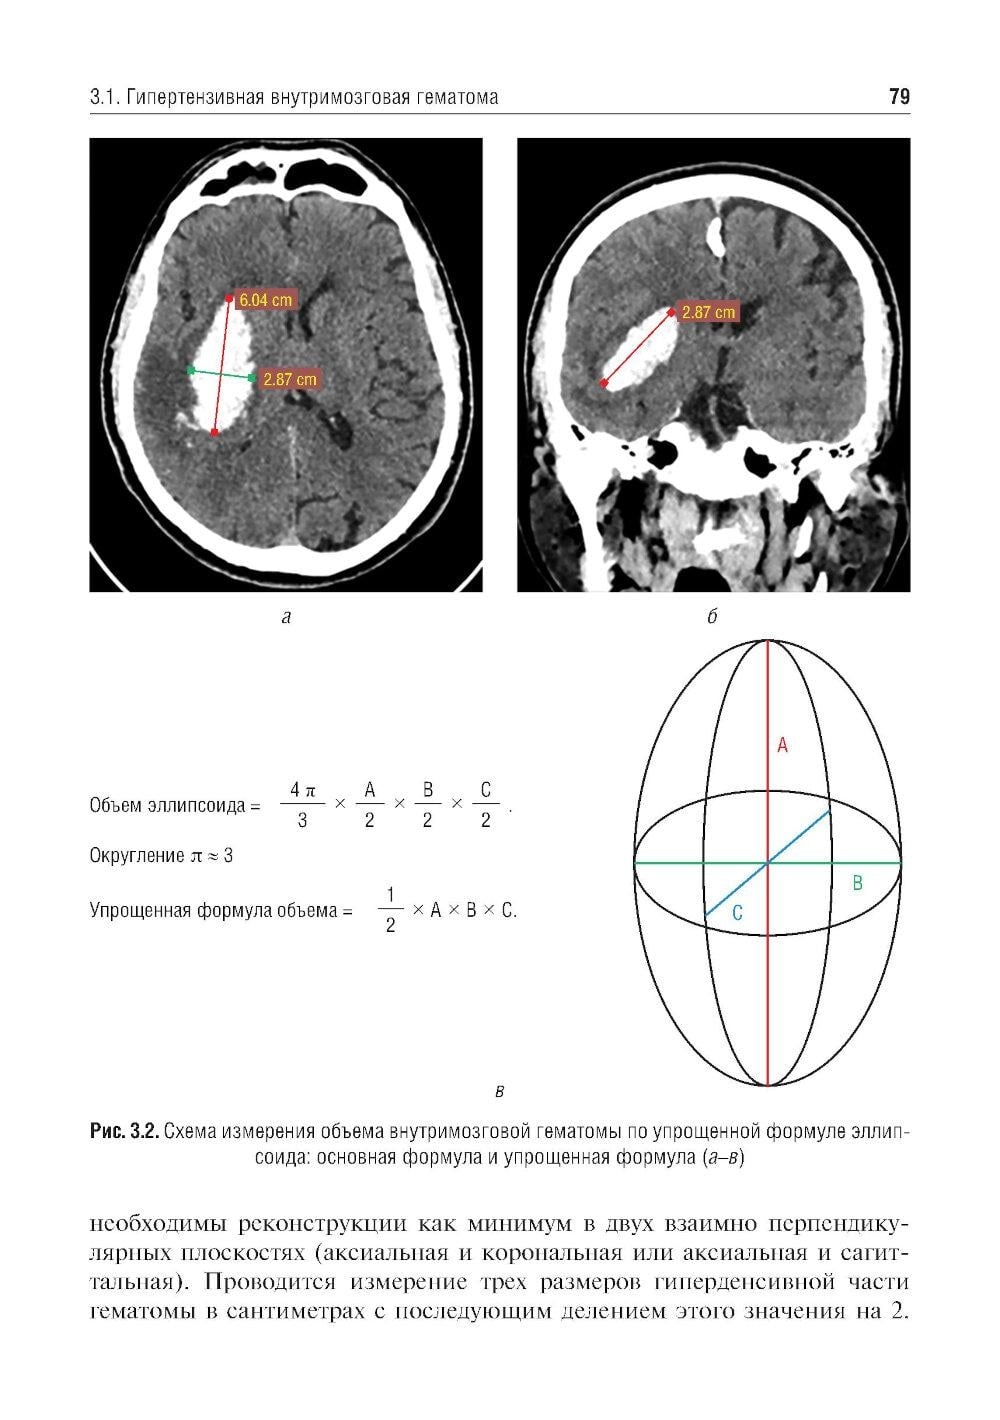

Учебное пособие составлено на основе действующих клинических рекомендаций. Представлены принципы формализованного подхода и формализованные шаблоны протоколов рентгеновской компьютерной томографии и магнитно-резонансной томографии при остром нарушении мозгового кровообращения и нетравматических внутричерепных кровоизлияниях.